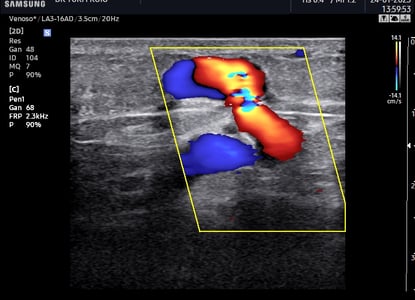

Ecografia Vascular

A ecografia vascular com Doppler avalia o fluxo sanguíneo em artérias e veias identificando obstruções, varizes e tromboses. É um exame não invasivo, essencial para diagnóstico e acompanhamento de doenças vasculares. Proporciona informações detalhadas para uma abordagem clínica precisa.